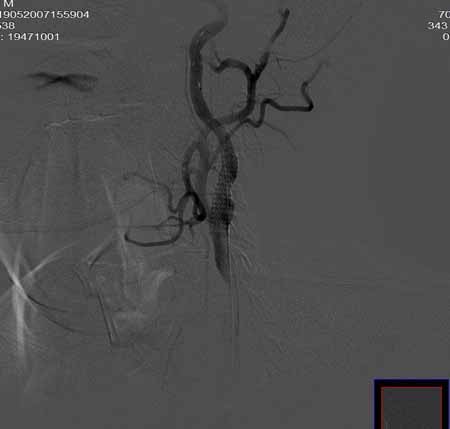

男,60岁。

腹主动脉、颈总动脉、颈内动脉狭窄支架置入术,最少放了三个支架吧,得十几万吧。

颈总动脉支架置入术。

指针宽了些

wallstent9*50可以全部覆盖,可以节约些

当然楼住的选择无可指责